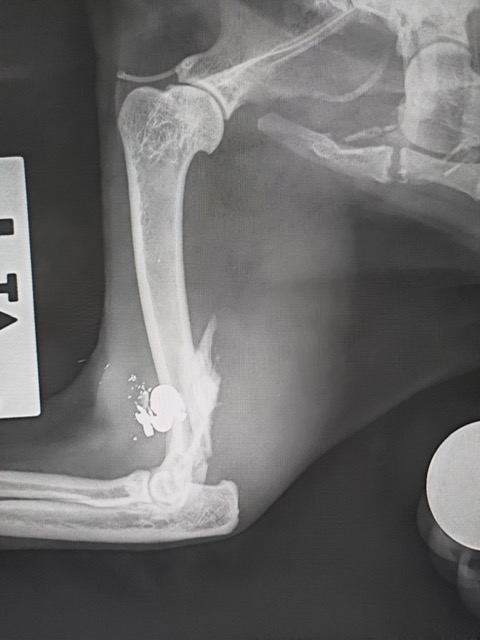

I pallini che hanno raggiunto il felino

Una delle due ha una zampa gravemente compromessa, "ma grazie all’impegno e alla professionalità dei dottori Laura Benedetti e Federico Vegni si sta lavorando per far arrivare una protesi speciale che possa permetterle di tornare a vivere con dignità", dicono dallo Scudo di Pan.

La situazione dell’altra gatta - fanno sapere - è ancora più critica: oltre alla zampa seriamente danneggiata, presenta numerosi pallini di piombo nel corpo. I veterinari stanno valutando con grande attenzione come intervenire per salvarle la vita.